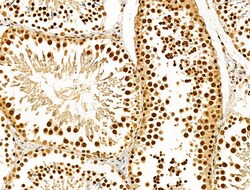

Invitrogen™ Phospho-AKT1 (Ser124) Polyclonal Antibody

Antibody detects endogenous levels of AKT1 only when phosphorylated at Ser124.

| Immunohistochemistry (Paraffin), Western Blot, Immunocytochemistry | |

| A synthesized peptide derived from human AKT1(Accession P31749), corresponding to amino acid residues around phosphorylated Ser124. | |

| Human, Mouse, Rat | |